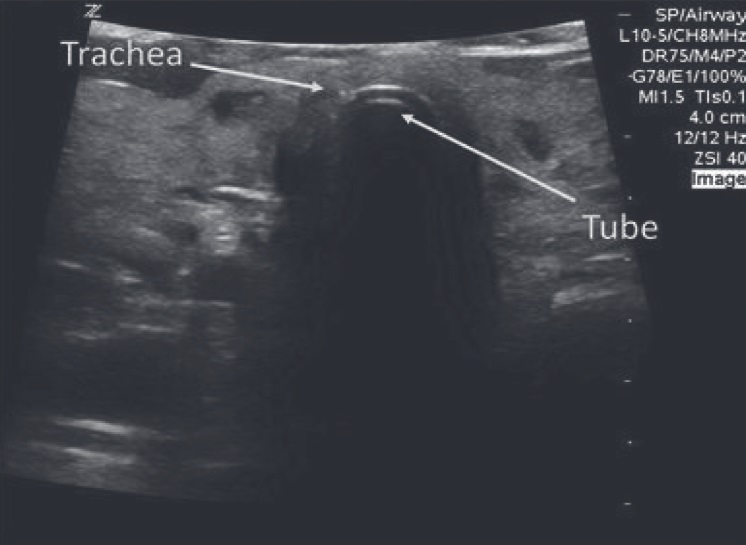

Allocation concealment was done by placing the groups in sequentially numbered opaque sealed envelopes using the SNOSE method. In the preoperative room, USG scanning and skin markings were performed for better visualization of the trachea and visceral parietal pleural interface (Figures 1 and 2). Upon arrival in the operating theater, standard monitoring as an electrocardiogram, non-invasive blood pressure, pulse oximetry, and capnography, was initiated. Baseline vitals were recorded. The intravenous injection line was secured patients were placed in Rapid Airway Management Position (RAMP) for laryngoscopy and intubation. Standard GA protocol was followed. All intubations were performed by senior anesthesia residents.

In Group T

(1) Probe placement: On the anterior aspect of the neck, just above the suprasternal notch in the transverse plane (depth 2.5 cm) as seen in Figure 1

Figure 1.

Download full-size image

Fig. 1. Pre Procedural Scan for Tracheal Ultrasonography